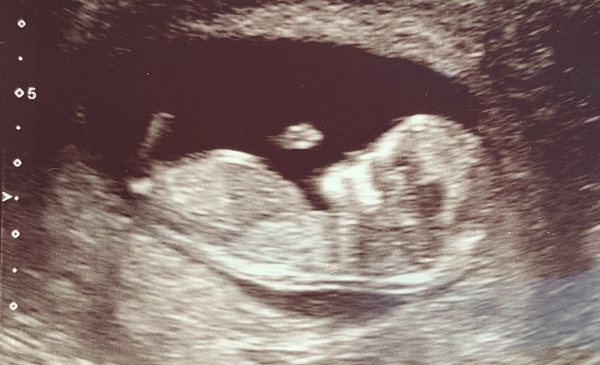

eskimod · 18/09/2019 20:09

@lonelyonee you're slim and I can defo see a little bump 😊

I had my scan today. She was pressing really hard on my belly! Didn't expect it to be that uncomfortable! Maybe it was because of my flab 😂 but heart beat was seen and it had a little wiggle. She put me back a day from what I calculated so my new due date is 28th March 2020.

Due March 2020 - FIRST BABY in late 20's

lonelyonee · 18/09/2019 22:47

@eskimod btw that scan is sooo good! Really fab! My edd from my calculations is 28th! So we shall see what's said Saturday. Pressing hard? Oh Jesus! Maybe sonographer was struggling to find baby? The last scan I had I'm sure it was fairly gentle, apart from that horribly cold gel! So exciting though! Glad everything is well with baba!

jlo6308 · 19/09/2019 19:19

Definitely a little bump there @lonelyonee, and congrats on the scan @eskimod! I’m just starting to feel nervous/anxious about mine tomorrow. I think because I’ve had barely any symptoms it still doesn’t feel real, just hoping everything is ok tomorrow 🤞🏼

jlo6308 · 20/09/2019 16:31

Yes! Scan was great thanks, everything all as it should be, so much to see compared to the little dot at 6 weeks! Due date has moved to 2nd April so not a March baby anymore, still going to tag along on this thread though if that’s ok 😂 good luck for tomorrow @lonelyonee!

jlo6308 · 20/09/2019 21:23

Here it is! I also had to empty my bladder as it was too full and the baby was all squished up 😂 so my advice is make sure your bladder’s full, but not full enough that you feel like you’re going to wee every time you walk 😂